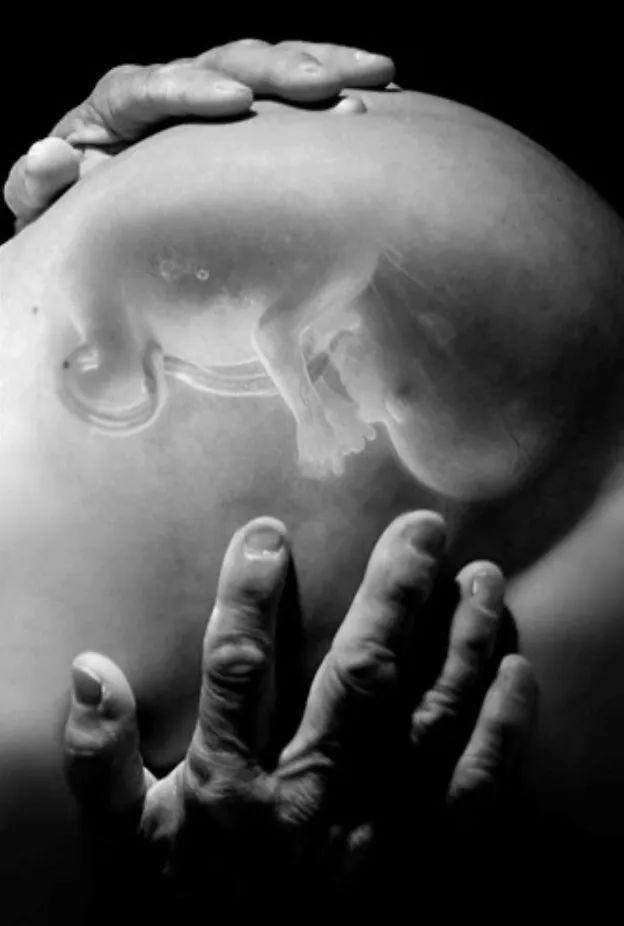

在41岁那年,她再次怀孕,迎来了第九个孩子。几个月过去,她的小腹像前几回一样隆起,出现胎动…

但她没有察觉,这次胎儿形成的位置是在腹部,而不是子宫…

因为是异位妊娠,没有足够的血液供应到婴儿,这个素未谋面的孩子在第7个月时就胎死腹中了。

就这样,胎儿继续留在她的腹中,她带着7个月的死胎生活,腹部变得越来越坚硬,时常疼痛难忍,但她宁愿忍耐身体病痛,也不想再遭遇异样的目光和评价,坚决不靠近诊所一步…

因为胎儿去世后一直留在腹部,免疫系统认为这只死胎对身体构成了威胁,对它发起猛烈攻击,于是,含钙的沉积物沉积在胎儿身上,逐渐将它包裹在钙化壳中,变成一块形似木乃伊的“石头”,也就是医学文献中记载的罕见出现的“石胎”。